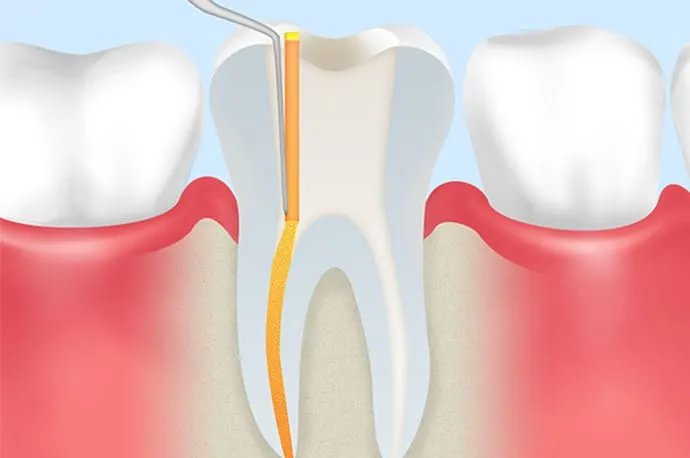

3.きれいな根管を維持する

根管内を清潔な状態にできたら、その環境を長く保つことが重要です。防腐作用のある材料やバイオセラミック系の糊材で根管内をすき間なく満たし、再び細菌が侵入しないようにします(根管充填)。

根管充填と土台作り

再来院時に問題がなければ、根管内に防腐剤の詰め物を行います(根管充填)。その後、感染を防ぐため、歯と強力に接着するレジンなどの材料で上からフタをし、歯の土台を作ります(築造)。

その後は、できるだけ早めに型採りを行い、仮歯や最終的な被せ物を作製していく流れとなります。